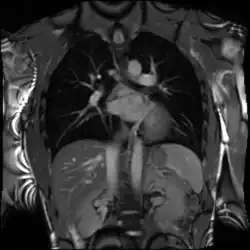

Cardiac magnetic resonance imaging (cardiac MRI, CMR), also known as cardiovascular MRI, is a magnetic resonance imaging (MRI) technology used for non-invasive assessment of the function and structure of the cardiovascular system.[2] Conditions in which it is performed include congenital heart disease, cardiomyopathies and valvular heart disease, diseases of the aorta such as dissection, aneurysm and coarctation, coronary heart disease. It can also be used to look at pulmonary veins.[3]

Combined with vasodilator stress, it has a role in detecting and characterizing myocardial ischemia due to disease affecting the epicardial vessels and microvasculature. Late gadolinium enhancement (LGE) and T1 mapping allow infarction and fibrosis to be identified for characterizing cardiomyopathy and assessing viability.[8] Magnetic resonance angiography may be performed with or without contrast medium and is used to assess congenital or acquired abnormalities of the coronary arteries and great vessels.[9]